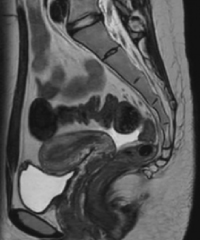

MRI検査室

当院では2023年11月より最新機種Philips社製1.5TMRI装置Ambitionを導入し運用を開始しました。従来装置に比べ撮像時間の短縮、画質向上また、新たな撮像方法による診断の質の向上が目的です。

-

- 頭部画像

- 胆のう・胆管・膵管

- 腰椎

- 女性骨盤

- 手指